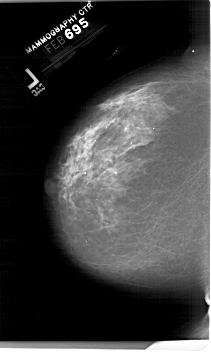

A_1999_1.RIGHT_MLO

RIGHT_MLO LINES 6196 PIXELS_PER_LINE 4306 BITS_PER_PIXEL 12 RESOLUTION 43.5 OVERLAY